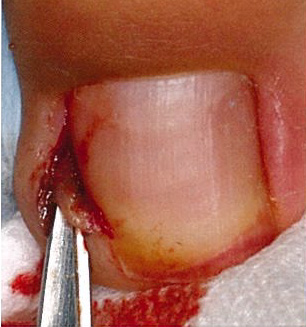

重症や難治性の方が対象です。皮膚に食い込んでいる爪甲側縁を必要最小限に切除し、刺さった状態を解除してあげることが大事です。局所麻酔を併用し、爪甲側縁を楔状に切除し、肉芽形成を伴う場合には肉芽も切除してしまいます。局所麻酔の痛みと出血がありますが、治療後は悩みの種であった痛みは数日内で治まり、皮膚の炎症は速やかに収束に向かいます。この方法では基本的に爪母が温存されることから、後遺症を残す可能性はほとんどありません。

④引き抜いた爪

⑤肉芽の切除